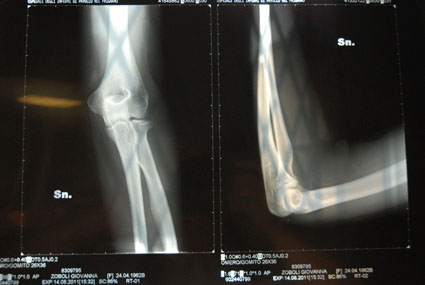

La frattura del gomito è un evento patologico che consiste nella frattura di una combinazione qualsiasi delle tre ossa che compongono l'articolazione del gomito.

La frattura può essere composta, scomposta, pluriframmentaria e con possibile lussazione.

Sono delle fratture frequenti in età adulta, il meccanismo patogenetico può essere dato da cadute a impatto diretto a terra del gomito in posizione flessa, oppure per trauma indiretto, ossia.